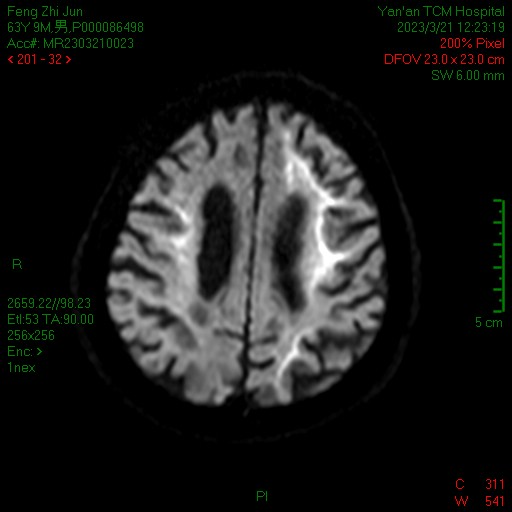

患者男性,63岁,因“头晕、行走不稳、反应迟钝2年,加重7天主诉”入院。曾辗转多家医院未能确诊。既往否认高血压、糖尿病及冠心病等病史。入院后北京大学第三医院陈璐教授及郭晓贤主任详细查体:记忆力减退,反应迟钝,指鼻试验欠稳准,跟膝胫试验欠稳准。定位高级皮层功能与小脑系统均受累,行头颅磁共振检查发现异常,脑病科团队高度怀疑神经元核内包涵体病,该病属于神经内科疑难病例,确诊需要进行皮肤病理活检与基因检测,需同多种疾病鉴别。

北医三院驻延脑病科专家陈璐教授擅长行皮肤、神经、肌肉活检手术,为患者进行了皮肤活检,填补了延安地区这方面的空白。随后启动了延安分院至北医三院绿色通道,与北医三院神经内科、病理科、检验科等多学科进行远程MDT会诊,同时皮肤活检及血液标本快递直送北京大学第三医院,标本病理回报支持神经元核内包涵体病(NIID),基因检测发现致病基因NOTCH2NLC,病理与基因诊断明确,为患者后续治疗明确了方向。